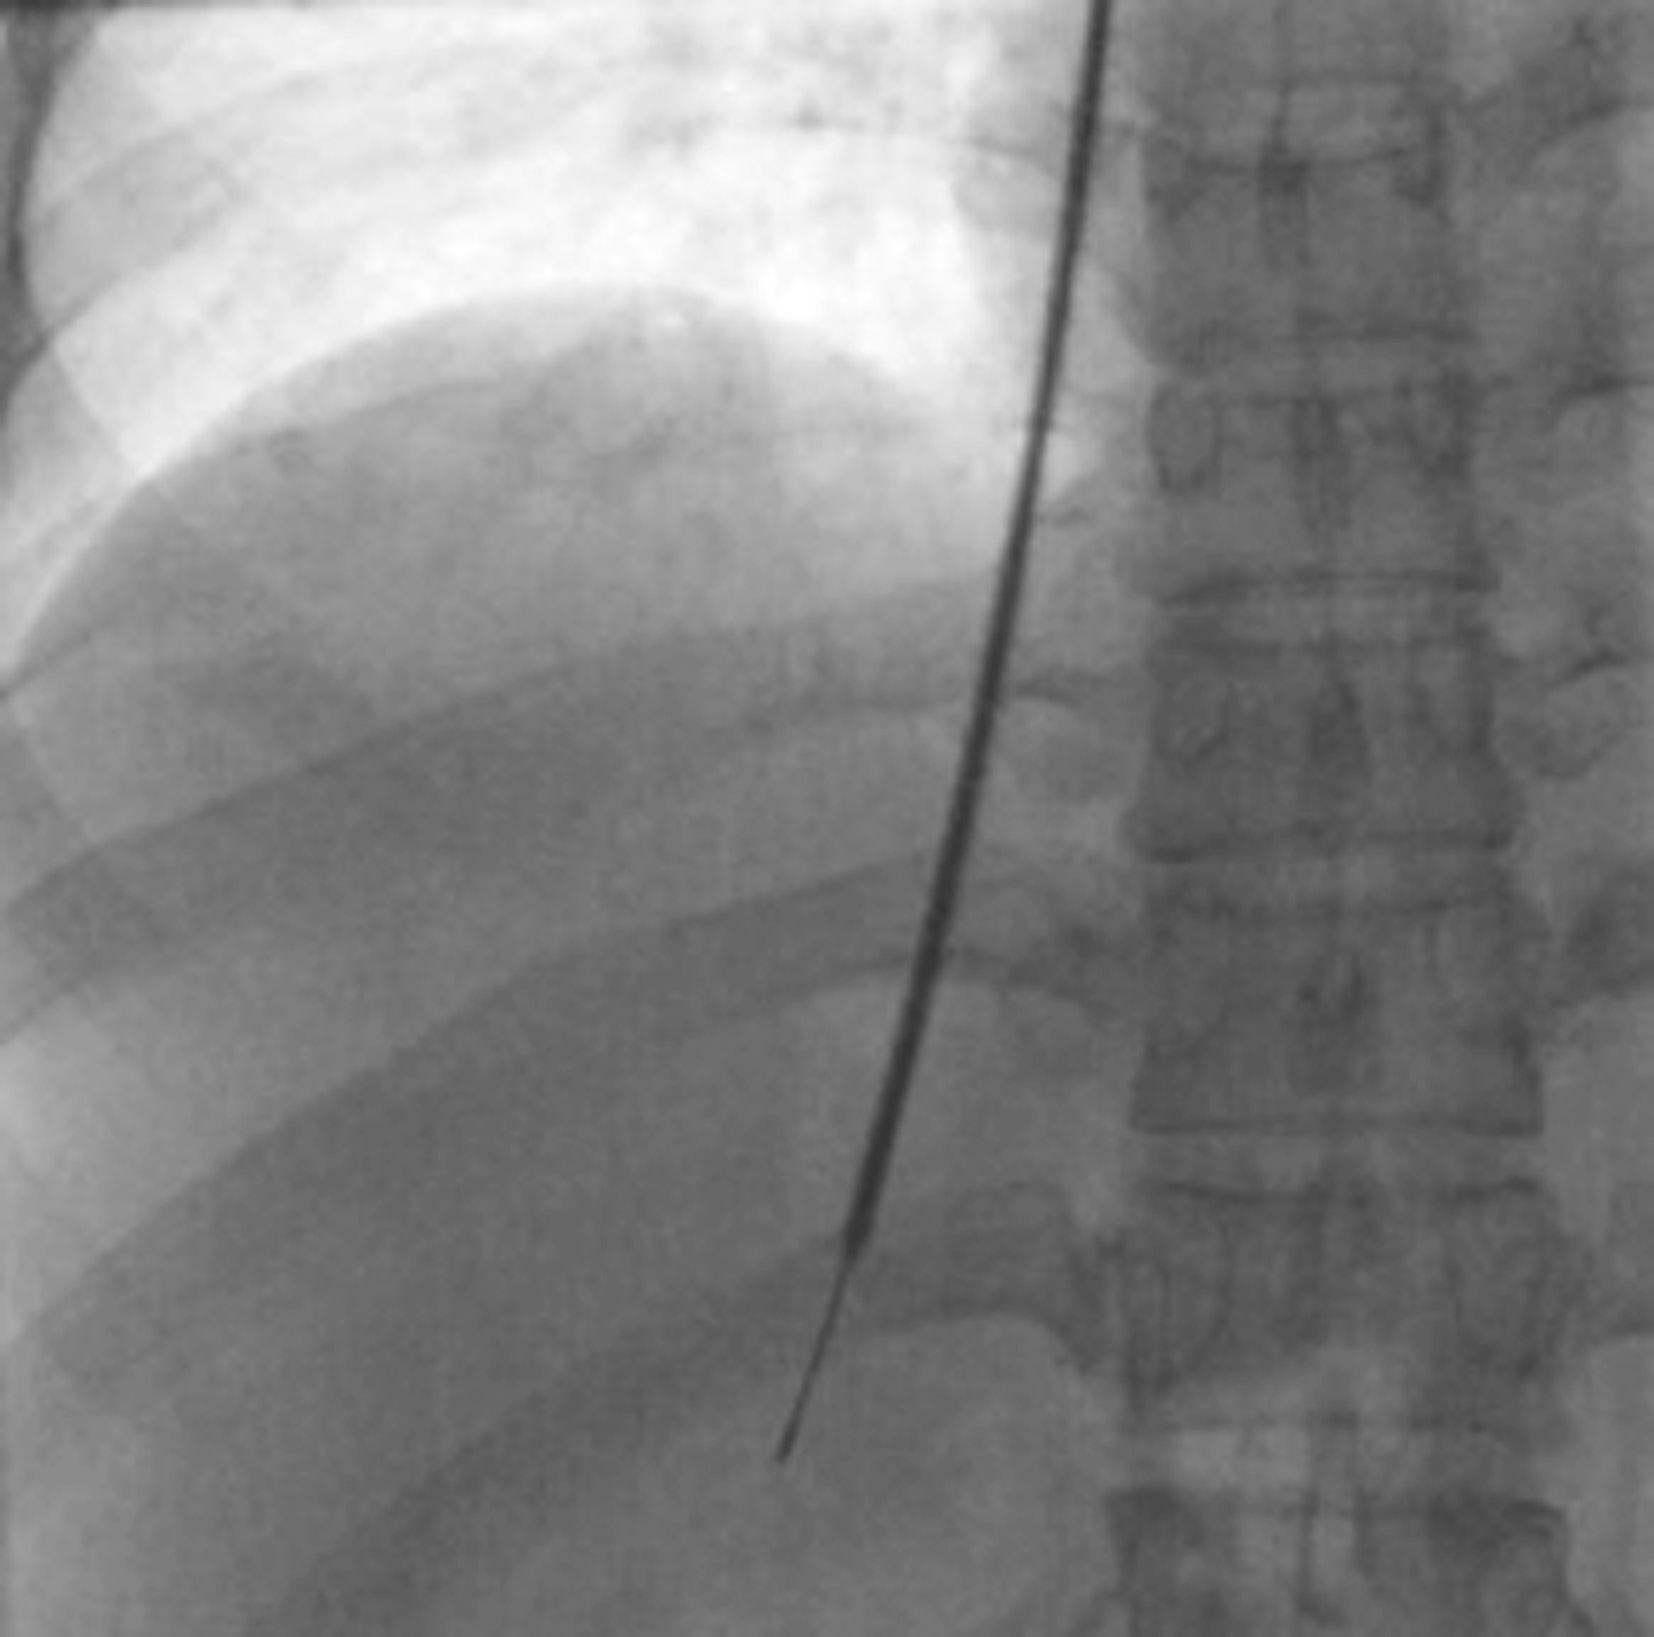

TJLB需要有经验的介入医生进行操作,患者仰卧于DSA检查床,常规予心电、血压及血氧饱和度监测。头左偏暴露右侧颈静脉区域,常规消毒、铺巾;2%利多卡因5mL局部麻醉后,采用Seldinger技术穿刺右侧颈内静脉,引入9F导管鞘(头端预成形为弯形),导管导丝配合将导管鞘经右心房进入下腔静脉;首先行下腔静脉DSA确认无明显下腔静脉狭窄,再将导管鞘进入肝静脉(常规选择肝右或肝中静脉),再造影确认肝静脉无明显狭窄闭塞(图5-22-1),其间分别检测右房、下腔静脉及肝静脉压力;将导管鞘头端进一步深入肝右静脉远端、距离下腔静脉3~4cm处,经鞘引入7F肝穿活检针;确认位置后嘱患者屏住呼吸,旋转导管鞘头端指向正下方,开启活检枪完成肝实质活检(图5-22-2);退出活检针,视获得肝组织大小决定是否再次获取肝组织,最后行肝静脉造影排除明显异常。术后患者平卧并监测心电、血压、血氧饱和度4h,术后24h 复查血常规、凝血功能等指标。

图5-22-2 经颈静脉肝穿刺活检